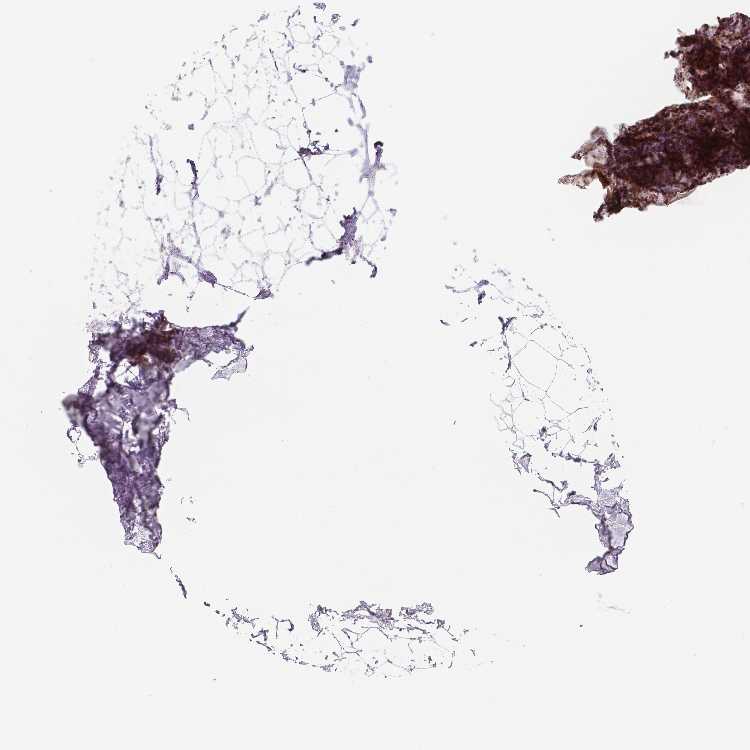

BREAST - Antibody stainingi

Antibody staining in the annotated cell types in the current human tissue is reported as not detected, low, medium, or high, based on conventional immunohistochemistry profiling in selected tissues. This score is based on the combination of the staining intensity and fraction of stained cells.

Each image is clickable and will lead to virtual microscopy that enables deeper exploration of all samples and also displays staining intensity scores, fraction scores and subcellular localization as well as patient and tissue information for each sample.

Antibody HPA029693Antibody CAB005017Antibody CAB068191

Adipocytes LowHighNot detected

Glandular cells LowHighMedium

Myoepithelial cells LowHighMedium